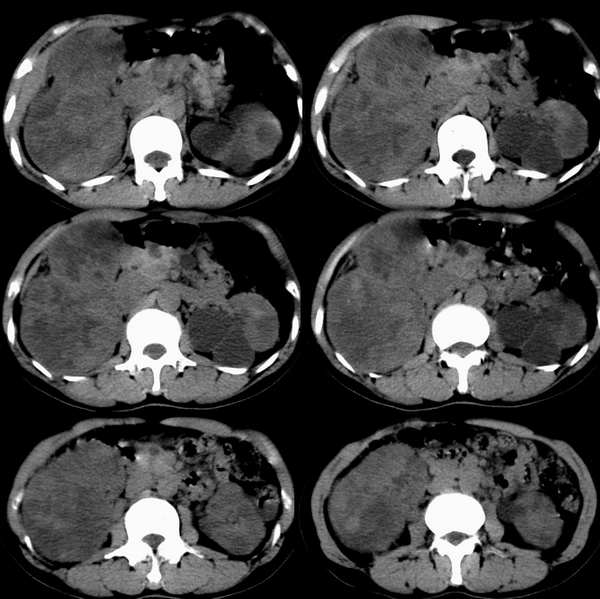

增强注药2小时后再次扫描

肝内胆管轻度扩张,肾门区及胰头区结构不清,胰腺多个囊性结构,考虑为胰头受侵,胰管的串珠状扩张可能大。

右肾癌  左多囊肾 胰腺(胰头周围淋巴结肿大)胰管扩张